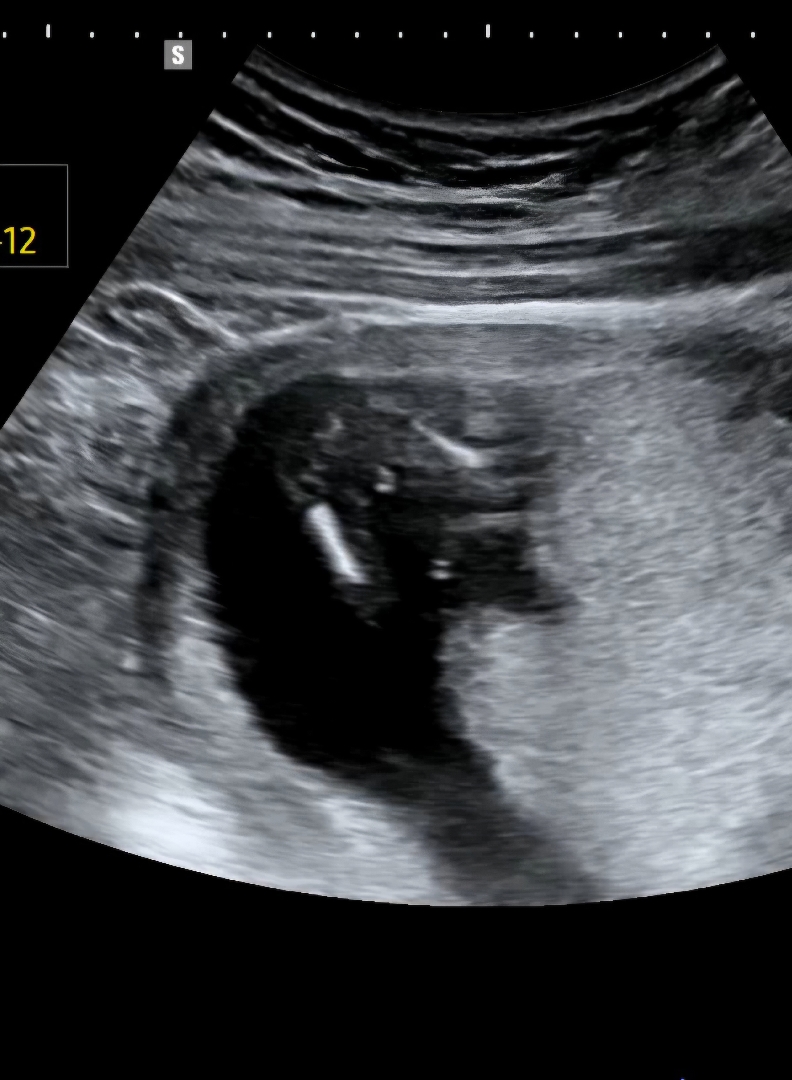

아들일까요 탯줄일까요..!!

13주 4일이에요!! 원장님은 아들50% 탯줄50% 본다고 하셨는데 어떻게 보이세요..?ㅎㅎㅎㅎㅎㅎ

15주인 제가 봤을땐 딸같아요

갹..!! 정말요..? 16주쯤 되면 확실히 알수있겠져..?ㅠㅠ 감사해요!!! 좋은 하루 보내세요💛